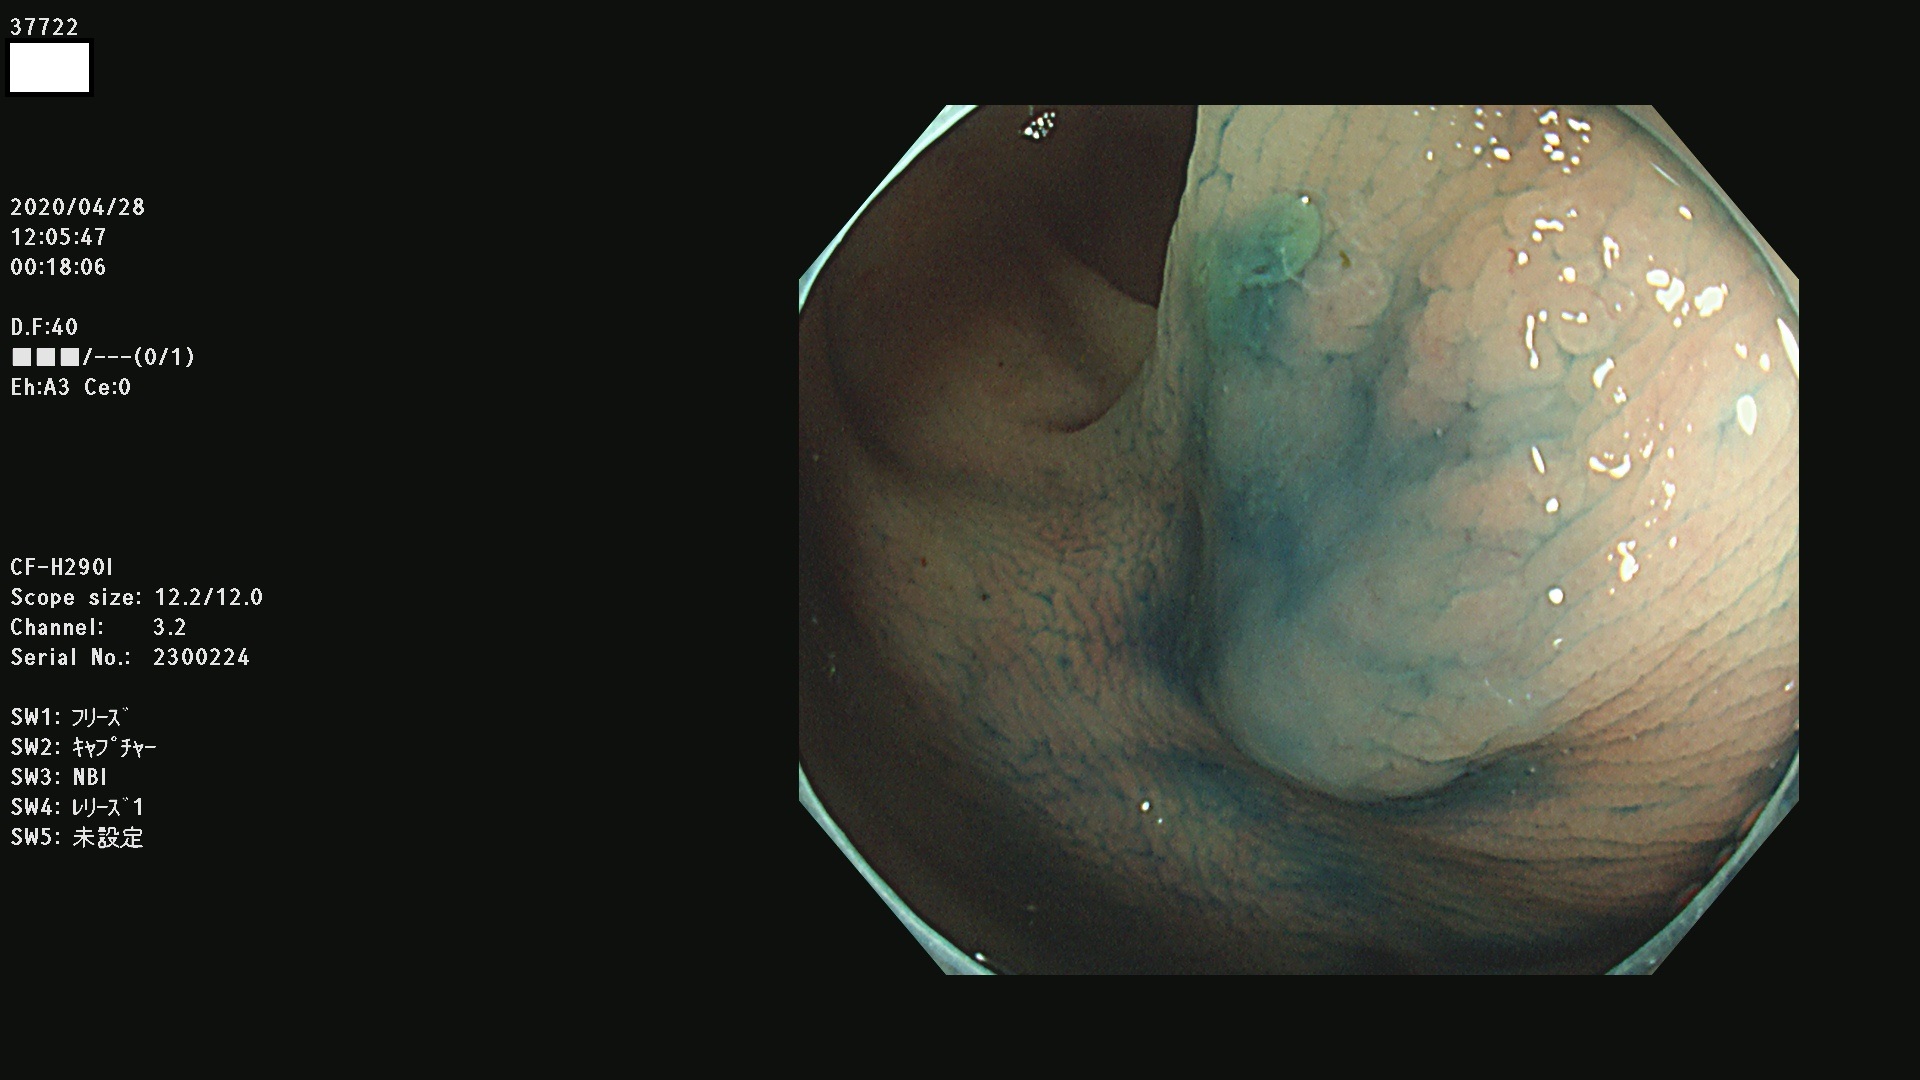

37700 37701 37702 37703 37704 37705 37706 37707(SSAPのみ) 37709 37711 37712 37715 37716 37717 37720 37722(SSAPのみ) 37724 37725 37726 37727 37728 37729 37731 37732 37733 37736(SSAPのみ) 37737 37739 37740 37741 37742 37744 37745 37748 37749 37750 37751 37752(SSAPのみ) 37753 37754 37755 37757 37758 37760 37761 37762(SSAPのみ) 37763 37764 37765 37766 37767 37768 37769 37771 37772 37774 37775 37776 37777 37780 37781 37782 37783 37784 37785 37787(SSAPのみ) 37788 37791 37792 37793 37794 37795 37799

発見困難で危険性の高い平坦型病変(上記100名より抽出)